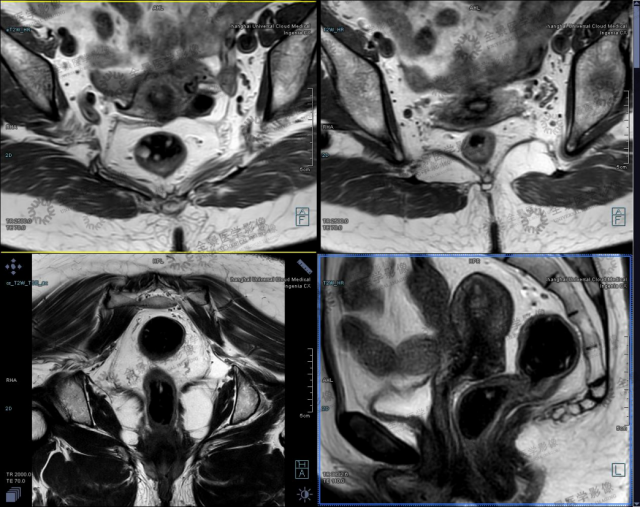

在 HR-MRI T2WI 上(如图所示),能清楚分辨直肠壁的三层结构即黏膜、黏膜下层和固有肌层以及直肠周围的系膜脂肪及筋膜,而常规 MRI 软组织分辨力低,不能分辨肠壁各层,因此术前分期准确性较 HR-MRI 明显低。

病例 1 男性,74 岁,2020 年 6 月 15 日因便血就诊,肠镜见距肛门齿状线 1 cm 处 2.5*3.0 cm 息肉样病变,病理示腺癌,现为术前明确盆腔状况,排除转移来诊。

直肠癌 T1 期,小视野 T2WI 显示肿块呈稍低信号,可见高信号的黏膜下层。